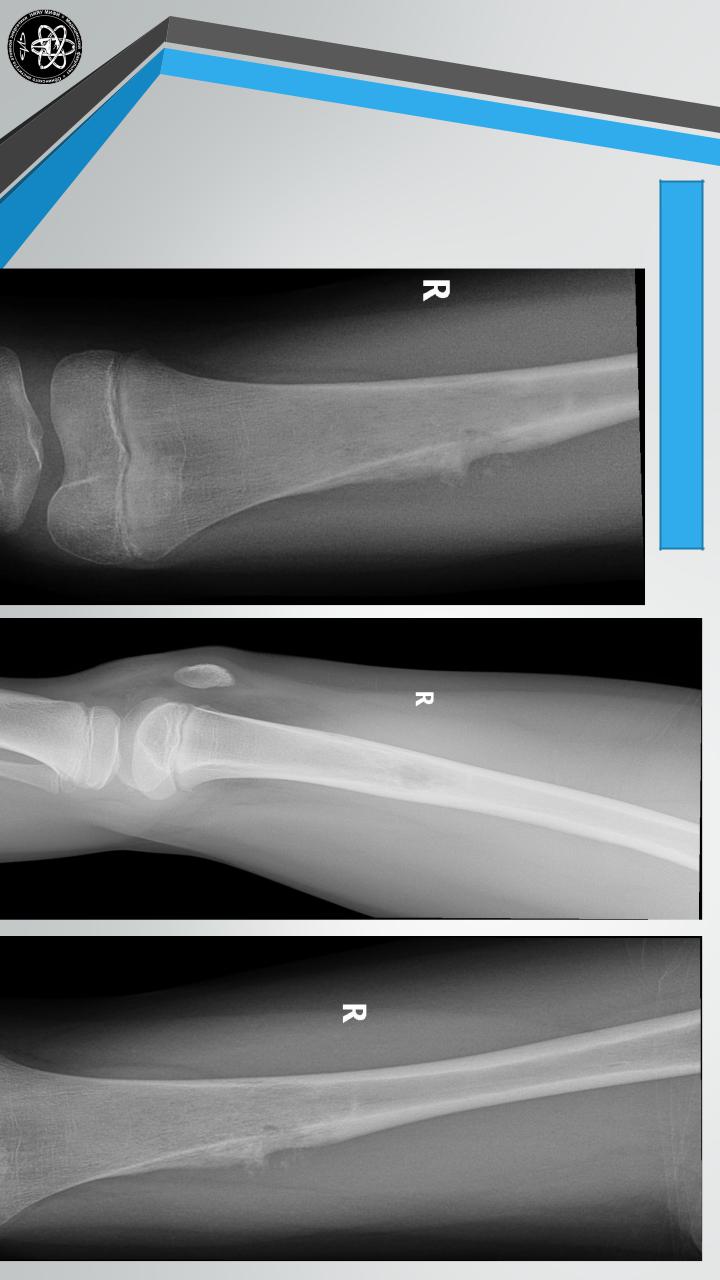

ОСТЕОГЕННАЯСАРКОМА

Частота — 23,6% всех костных опухолей и 46,5% всех

злокачественных опухолей.

Поражаемый возраст — 10-23 года, но наблюдаются и в

других возрастных группах.

Излюбленная локализация — дистальный конец

бедренной кости, большеберцовая, плечевая кости.

Чаще поражаются мужчины.

Клиническая картина — боль, быстрый рост, сосудистая

сеть в области опухоли, при аускультации можно

слышать шум над опухолью, местная температура

повышена.

Длительность течения — 6 месяцев-2 года.

Рентгенологически

остеолитическая

или

остеопластическая формы, “Козырек”, “спикулы”. Лабораторные сдвиги — СОЭ нарастает до 30-50 и

более

мм/час,

растет

щелочная

фосфатаза.

Метастазирует чаще в легкие.

Лечение

комплексное

хирургическое,

медикаментозное. Прогноз неблагоприятный.